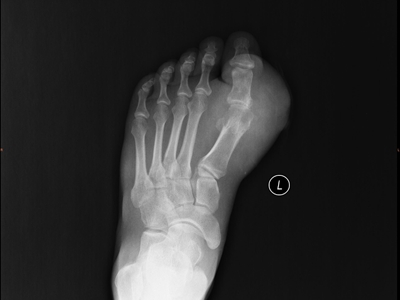

痛风病程较长,常反复发作而迁延不愈形成痛风石,是痛风的特征性临床表现,常见于指关节、第一跖趾关节、耳廓等处。外观为隆起、大小不一的不规则的黄白色赘生物,表面菲薄,破溃后排出白色粉状或糊状尿酸盐结晶物,经久不愈,但较少继发感染。部分患者伴有肾结石及肾脏病变。